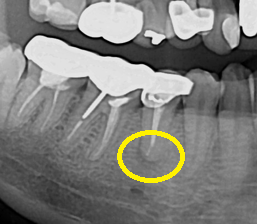

오래전에 신경치료를 받았는데 언제부턴가 통증이 생기셨다고 내원하신 환자분이십니다.

타진 검사 결과 두 번째 작은 어금니가 통증의 원인으로 판단 됩니다.

X-RAY에서 뿌리 근단부에 염증이 생겨서 기존에 있던 크라운을 제거하고 재 신경치료를 시작하기로 했습니다.